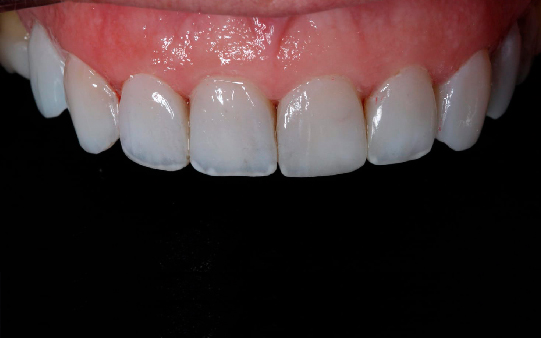

Protocolo em Resina Acrílica: boa estética, acessível, indicado para reabilitações com ótimo custo-benefício.